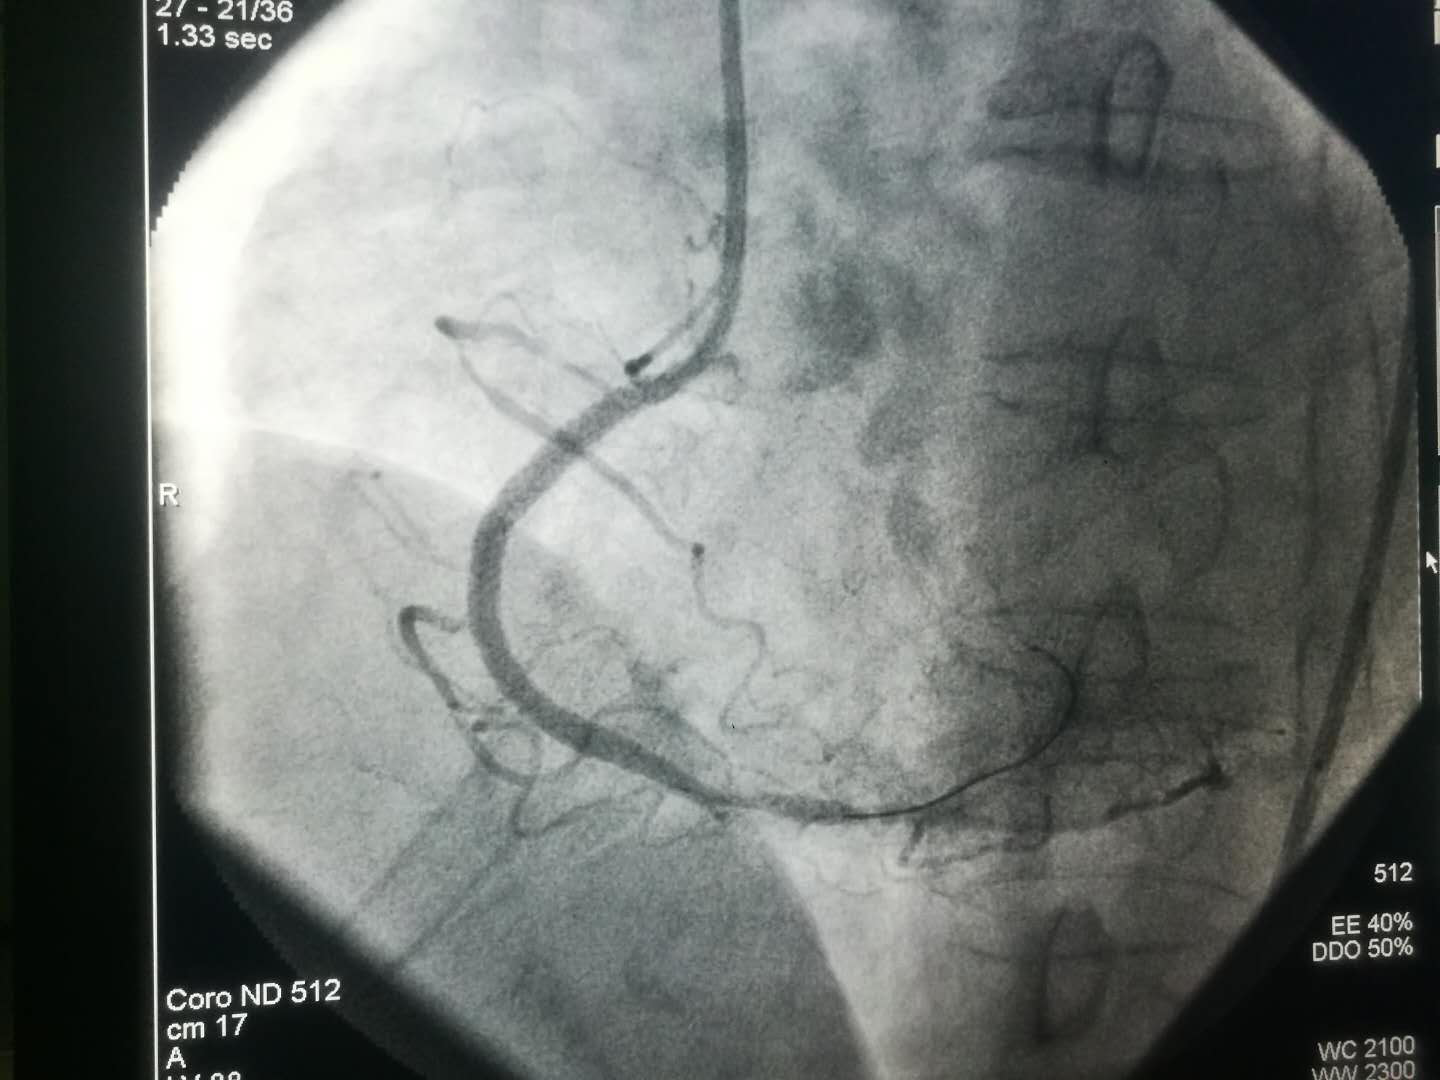

2019新年伊始,文理病区开展了首例冠状动脉造影术及冠状动脉支架植入术。

1月4日中午,文理门诊贾丽萍主任接诊一名胸痛患者, 经马会军主任急会诊,患者为急性冠脉综合征,立即组织救治并开通绿色通道。总院火速派出救护车接患者实施急诊冠状动脉造影术。患者及家属感动地说:“没有想到在分院就诊能享受到三甲医院的诊疗技术与护理服务。”对我院医疗护理服务的诊治技术、诊疗过程的服务及如此便捷快速的诊治流程,感到非常满意。虽然分院距离总院有数千米路程,但丝毫没有影响到分院三级医院服务的延伸。

1月8日上午患者术后在李同华主任的协助下完成文理病区首例冠状动脉造影术加冠状动脉支架植入术。术后患者转入心内四病区监护48小时,1月9日患者平安转回我科继续治疗。整个转诊过程无缝衔接,配合顺畅心血管病医院的各位主任护士长们纷纷表示,只要文理病区需要,术后患者可以转往心血管医院任何一个病区监护。距离无法阻隔我们发展的脚步,无法阻隔我们团结一致为患者服务的信心。